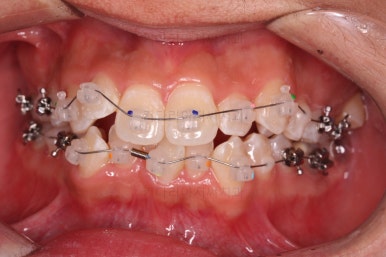

초진 시 입안의 모습입니다.

앞니가 많이 삐뚤고, 송곳니가 부각되어 덧니처럼 보이네요.

장치를 처음 부착한 모습입니다.

이번 환자분이 선택하신 장치는 데이몬 클리어라고 하는 자가결찰 세라믹 장치인데요.

흔히들 아시는 클리피씨 장치 등등에 비해 현존하는 브라켓 중에 가장 심미적인 장치입니다.